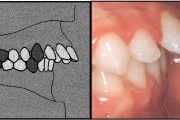

kahepoolse lõhega lapse hambumus

Valehambumus

Hammaste asendianomaaliad on tingitud tavaliselt arenguhäirest.